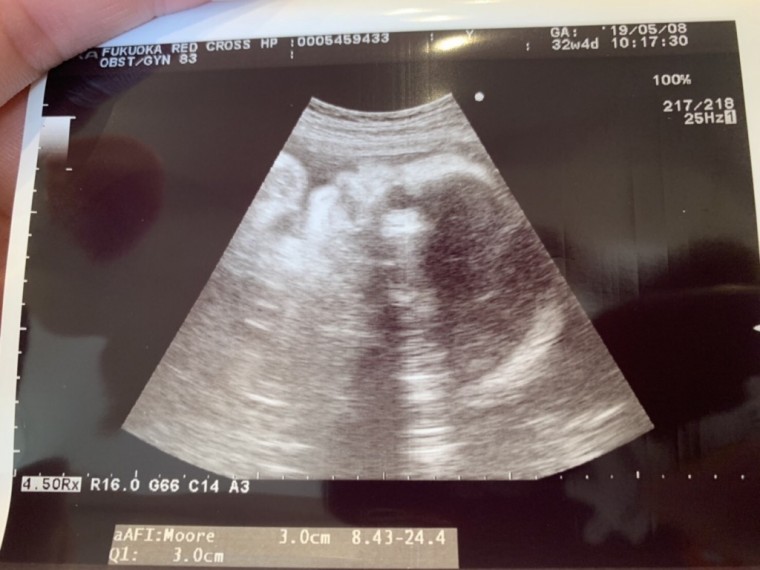

妊娠9ヶ月(32週4日)撮影日:2019年5月08日

-

血液検査の結果

鉄分が足りないらしい。食事で様子を見ることに。